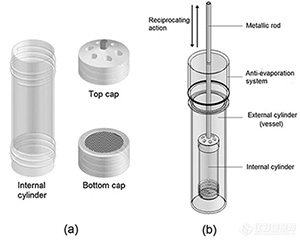

一、往複筒法的來源口服藥物(wù)的生物(wù)利用(yòng)度與治療效果主要取決于制劑在胃腸道中(zhōng)的釋放與吸收。快吸收的藥物(wù),···